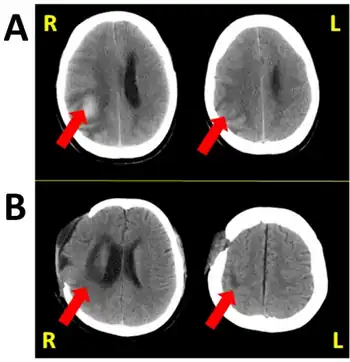

| Hemispatial neglect is most frequently associated with a lesion of the right parietal lobe (in yellow, at top). | |